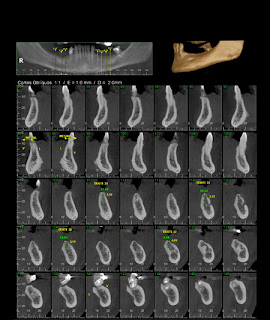

Tomografia Computadorizada Cone Beam